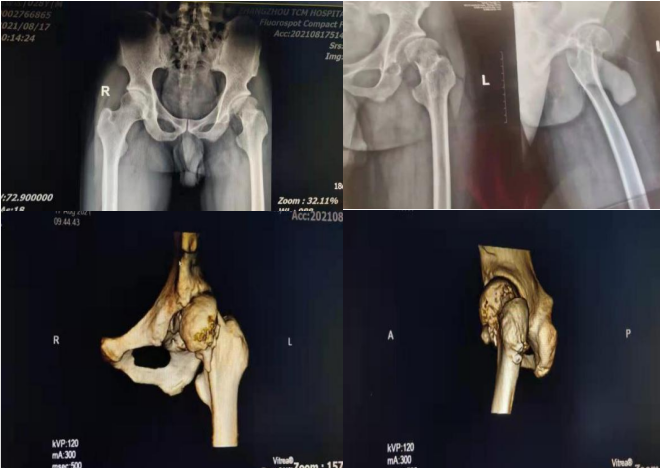

患者小吳,男性,28歲,一天前不慎跌撲致左髖部疼痛活動(dòng)受限,在外未經(jīng)診治,到我院骨傷科門診求診。入院診斷:1.左股骨頸骨折(頭下型)2.左髖關(guān)節(jié)發(fā)育異常關(guān)節(jié)半脫位。

術(shù)前

小吳12歲時(shí)因“左髖關(guān)節(jié)滑膜病變”在外院手術(shù)治療,術(shù)后小吳左下肢短縮、跛行,左髖關(guān)節(jié)活動(dòng)受限。此次受傷,經(jīng)相關(guān)檢查回報(bào),小吳左髖關(guān)節(jié)發(fā)育異常,股骨頭向前旋轉(zhuǎn)畸形,呈半脫位狀態(tài),股骨頭及頸部明顯較健側(cè)小,股骨頸前傾角增大約45度(正常約15度),股骨頸變短,頸干角變大約150度(正常約127度),左髖關(guān)節(jié)半脫位。